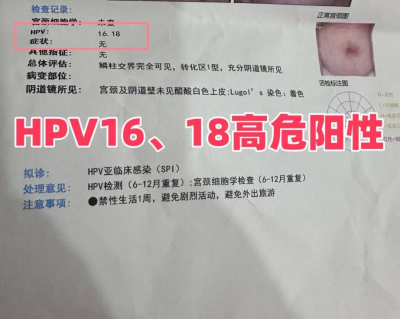

HPV16、18型高危阳性

做为教师的我,查询很多资料后非常清楚的知道HPV意味着什么,它会造成什么样的后果。但我怎么都没有想到HPV感染会让我饱受折磨。生完孩子后,下面总感觉不舒服。恰好到了体检的时候我也查了HPV,结果查出HPV16、18高危阳性。

看到报告单那一刻,身子都站不稳,挺受打击的,心情非常难受……说实话,焦虑了有一段时间,特别担心恶变。最恐怖的是我发现脖子上长了恶心的扁平疣,阴道变的特别脆弱,和老公房事也受到影响,老公后来都不爱靠近我,不和我在一个床上睡觉。